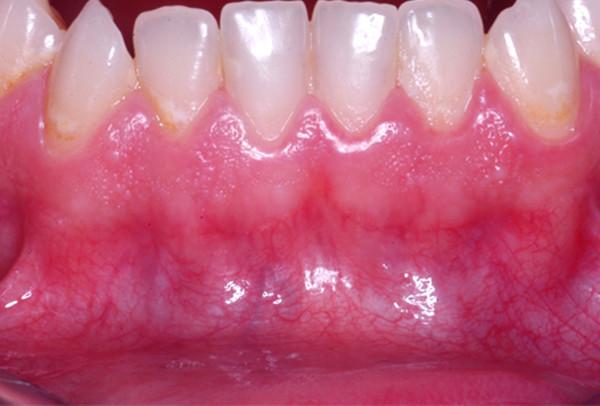

Besides the color of the teeth the color of the alveolar gingiva plays a crucial role in esthetic rehabilitation in dento-alveolar treatment. Whereas nowadays the color of the teeth can be determined exactly and individually, the specific influence of the red color of the gingiva on treatment has not been assessed yet. The aim of this study was to evaluate the vascularization as the basis for gingival esthetics.

Standardized photographs of defined areas of the alveolar gingiva in operated and non-operated patients were taken and assigned to groups with same characteristics after color comparisons. In addition, histologic and immunohistologic analyses of gingival specimens were performed for qualitative and quantitative assessment of vessels and vascularization. Finally, colors and number of vessels were correlated.

Our results demonstrated three different constellations of colors of the alveolar gingiva in healthy patients. The operated patients could not be grouped because of disparate depiction. There was a clear correlation between color and vessel number in the alveolar gingiva.